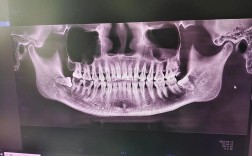

临床技术方面,林教授擅长将传统矫治理念与现代数字化技术深度融合,他主导开展的“3D打印个性化矫治器设计”“数字化微笑分析与重建”等项目,显著提升了复杂病例的矫治精度与效率,针对不同患者的需求,他形成了以“精准诊断-个性化方案-动态调整-长期稳定”为核心的全流程诊疗体系,尤其在高难度骨性错颌畸形矫治、唇腭术后继发畸形修复等领域,通过联合正颌外科、牙周多学科协作,实现了功能与美学的完美统一,以下是其主要技术方向与优势概览:

| 数字化精准矫治 | 复杂病例(如埋伏牙、多生牙) | 3D导航定位、误差控制在0.1mm内 |

A1:林教授的个性化方案基于“三维诊断”体系:首先通过数字化口扫、CBCT、头影测量等获取患者口腔结构与面部美学的精准数据;其次结合年龄、生长发育阶段、口腔习惯、职业需求等制定差异化目标;最后在矫治过程中动态调整,儿童患者侧重早期引导生长,成人患者兼顾效率与美观,老年患者则优先考虑口腔功能与牙周健康,真正实现“一人一方案”。